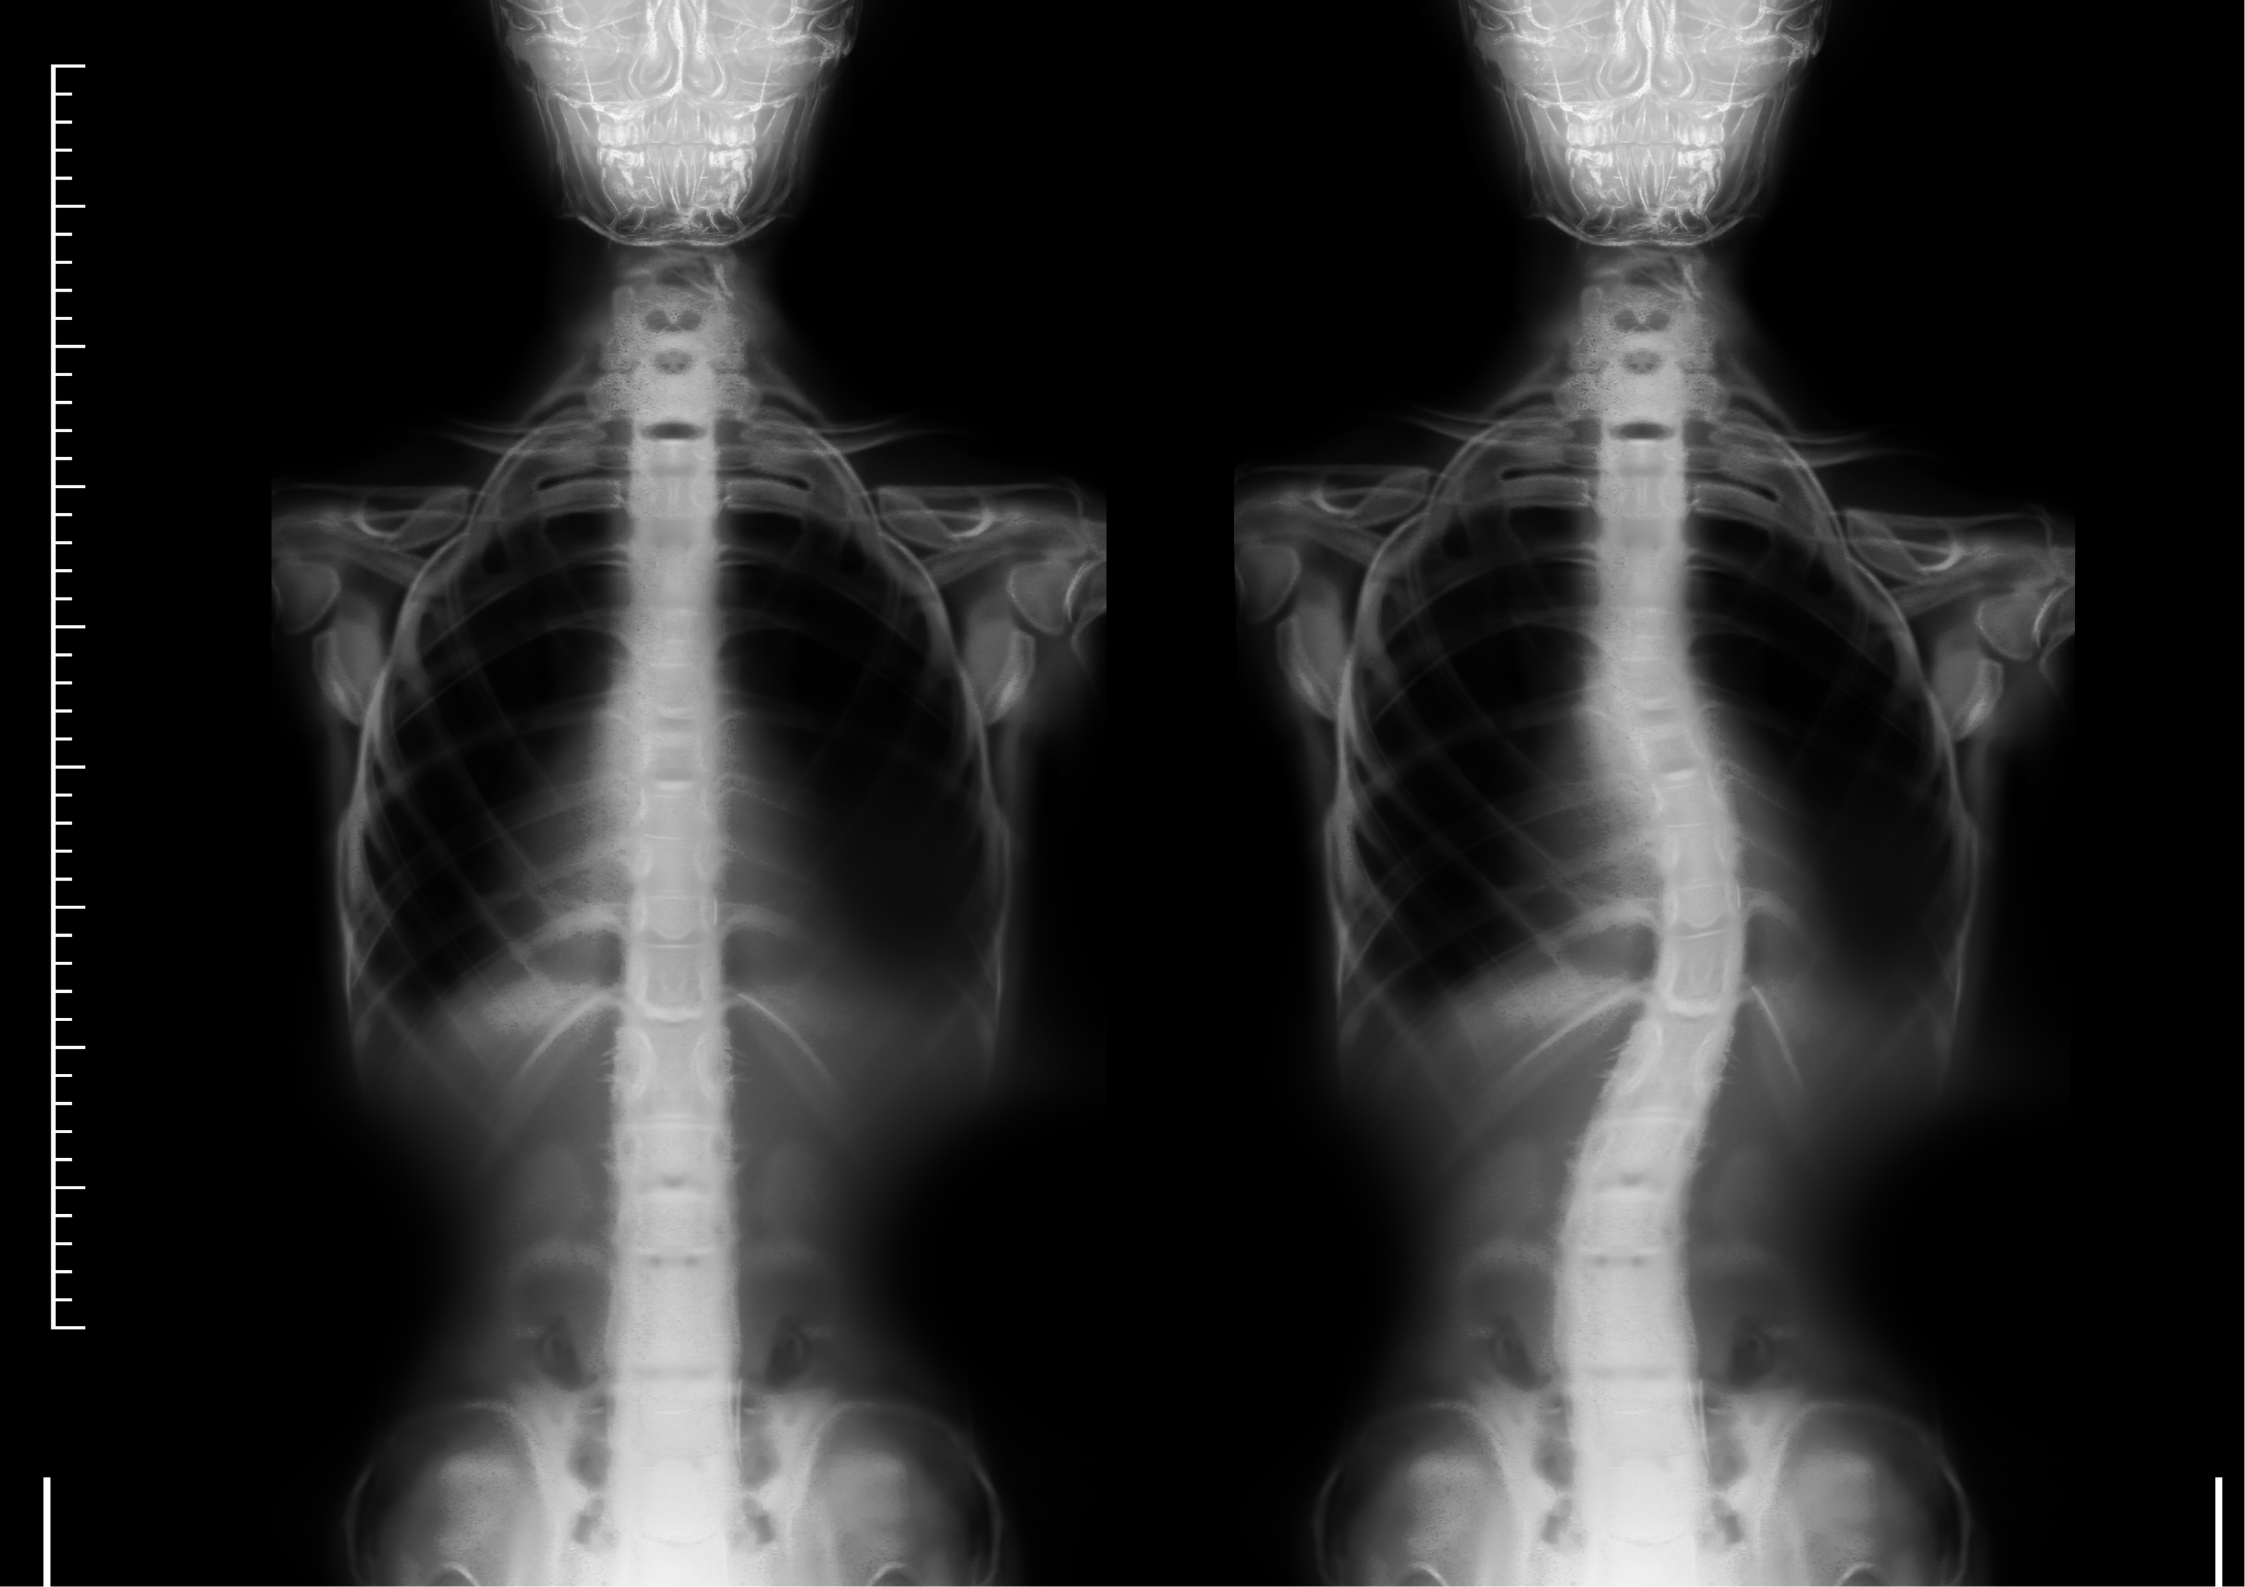

First: What Is Scoliosis?

Scoliosis is a condition where the spine curves sideways — typically into an “S” or “C” shape. It’s most commonly diagnosed between the ages of 10–18, often during a growth spurt.

There are a few different types:

Idiopathic Scoliosis: The most common in teens, with no known cause

Congenital Scoliosis: Present from birth due to spine malformation

Neuromuscular Scoliosis: Related to nervous system or muscular conditions